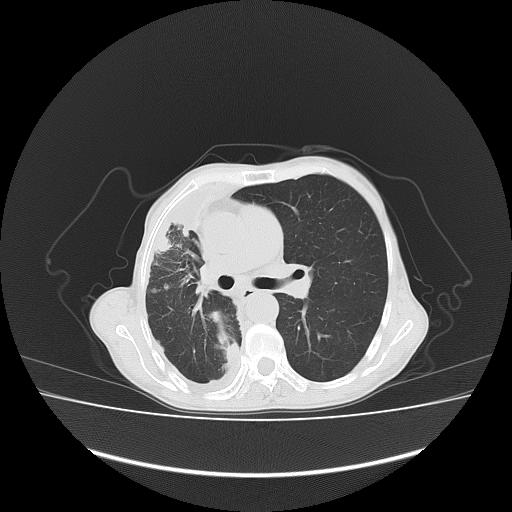

标题: CT16930:女 59 胸痛6个月 胸水脱落细胞学见瘤细胞 [打印本页]

可见多发肺内病灶,且胸膜病灶较多有圆球状而非丘状,多考虑胸膜转移瘤伴胸腔积液,右侧胸廓缩小固定,且部分病灶呈丘状,尚不除外恶性胸膜间皮瘤伴肺内转移

右侧胸膜增厚,局部呈结节状增厚,右侧胸腔少量积液。双肺未见确切肿块影。纵隔未见淋巴结肿大。气管、支气管通畅。考虑右侧胸膜间皮瘤(恶性?)可能性大。不除外癌性胸膜炎。

恶性胸膜间皮瘤伴肺内转移可能性大;或胸膜、肺内均为转移瘤,左肺下叶亦见多发小结节影。

右侧胸廓塌陷,右侧胸膜广泛增厚并见多发胸膜结节,右侧少量胸腔积液并包裹。

右侧广泛胸膜增厚,局部呈结节状增厚,右侧胸腔少量积液。双肺未见确切肿块影。纵隔未见淋巴结肿大。气管、支气管通畅。考虑右侧胸膜间皮瘤(恶性?)可能性大。支持!

右侧胸膜转移瘤,原发灶可能就在在右肺,另外建议检查右侧乳腺.

右胸腔结节均考虑来自胸膜(部分来源于叶裂),考虑胸膜间皮瘤或转移瘤.